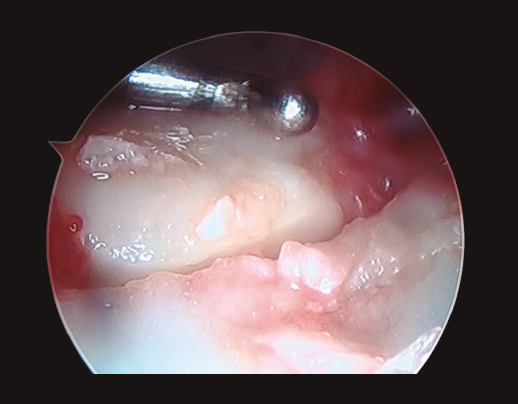

- La presencia del drive-through sign a nivel mediocarpiano en uno o ambos ligamentos interóseos, indicativa de una lesión completa de los mismos(3,9,17)(Figura 5). En estos casos, generalmente existe una inestabilidad asociada del hueso semilunar a la exploración artroscópica. Las lesiones de grado I y II de Geissler/Lindau se trataron mediante termocoagulación simple con vaporizador(3,20). En el caso de las lesiones de grado IV (lesión ligamentosa completa), se asoció al procedimiento anterior una fijación temporal con agujas de Kirschner (escafoides-semilunar , escafoides-grande y piramidal-semilunar) durante un periodo de 6 semanas(3,20)(Figura 6). Las lesiones de grado III se trataron de una manera u otra dependiendo de la presencia o no de inestabilidad del semilunar en la exploración artroscópica de la articulación mediocarpiana(3,20), a pesar de que trabajos como el de Yoshida et al.(15) ponen de manifiesto que la estabilización temporal con agujas de Kirschner de las lesiones ligamentosas de grado III y IV conducen a mejores resultados que la ausencia de tratamiento de las mismas.

Figura 5. Lesión completa del ligamento interóseo lunopiramidal observada desde el portal de visión mediocarpiano radial.